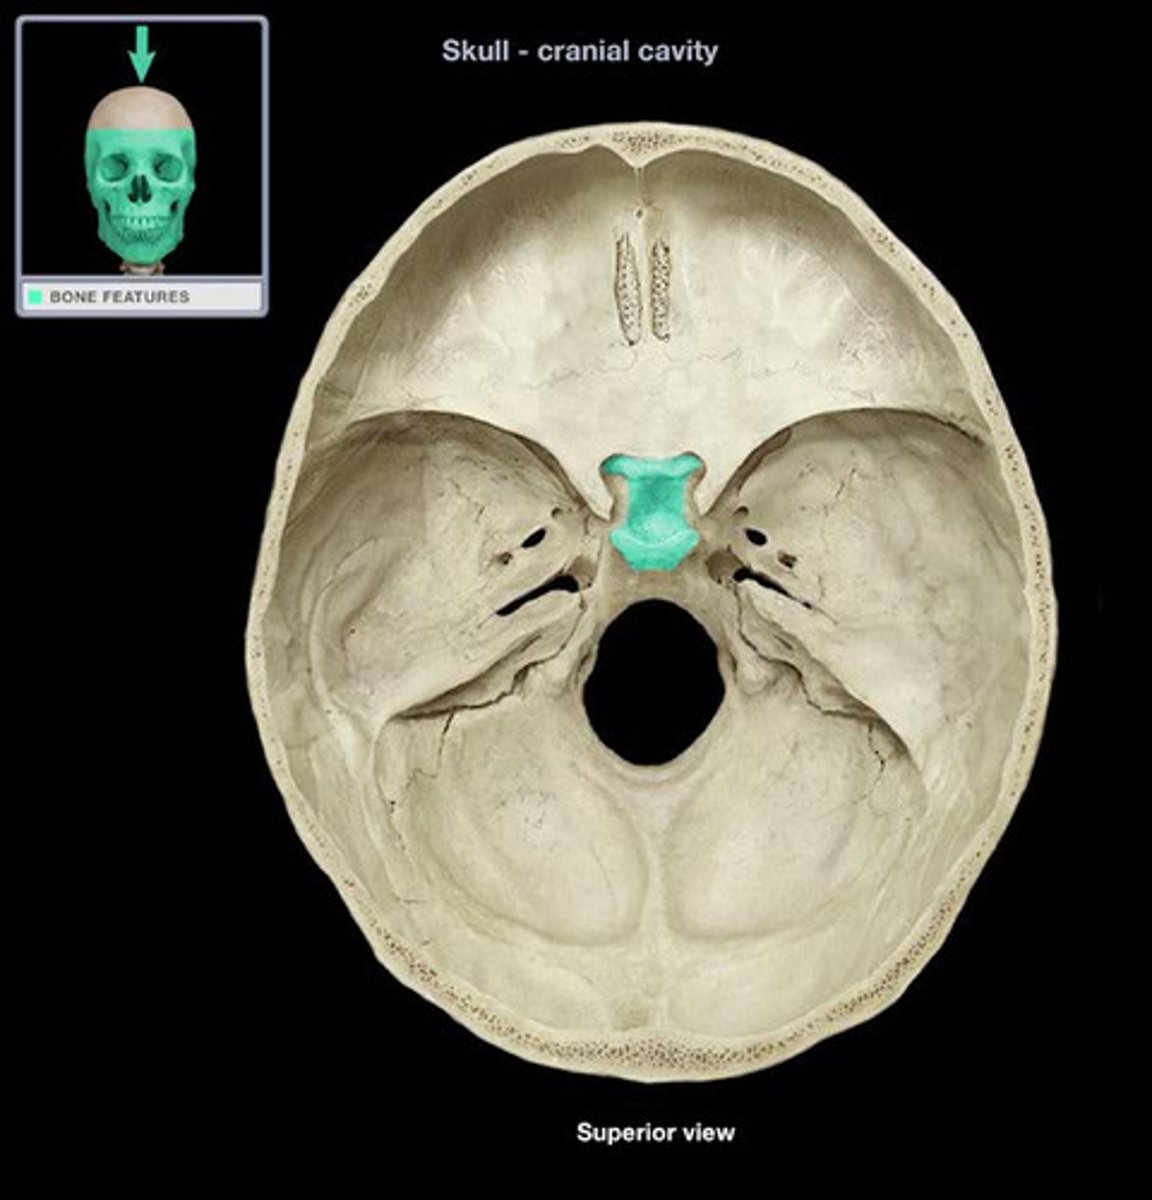

Sphenoid

Sphenoid

Sphenoid

Sphenoid

Pituitary Fossa

Name the dip